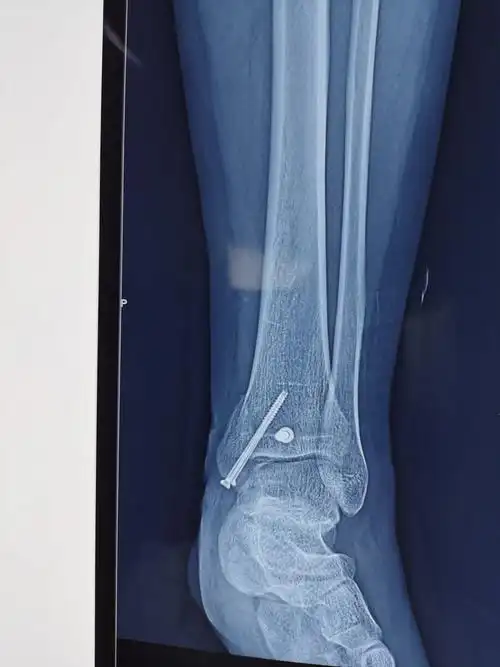

踝关节